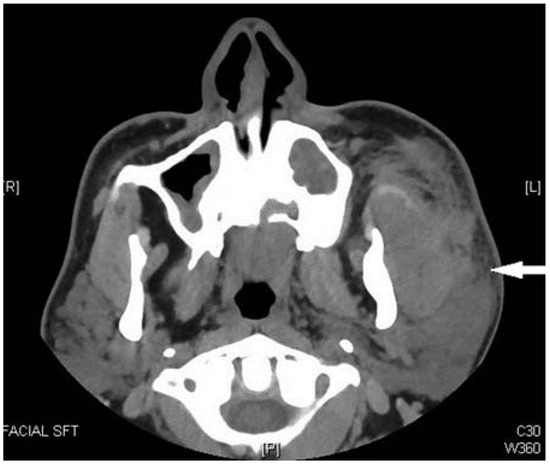

Despite a paradigm shift in anesthesia and trauma airway management, the craniomaxillofacial fracture (CMF) patients continue to pose a challenge. A prospective study was planned between April 2007 and March 2015 to investigate the safety, efficacy,...